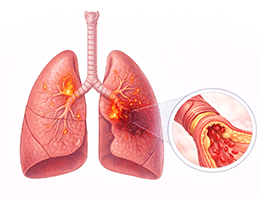

폐렴 (Pneumonia)

기관지염 (Bronchitis)

천식 (호흡기계 (기관지, 폐))

만성폐쇄성폐질환 (Chronic Obstructive Pulmonary Disease)

폐기종 (Emphysema)

기관지확장증 (Bronchiectasis)

폐섬유증 (Pulmonary Fibrosis)

기관지천식 (Bronchial Asthma)